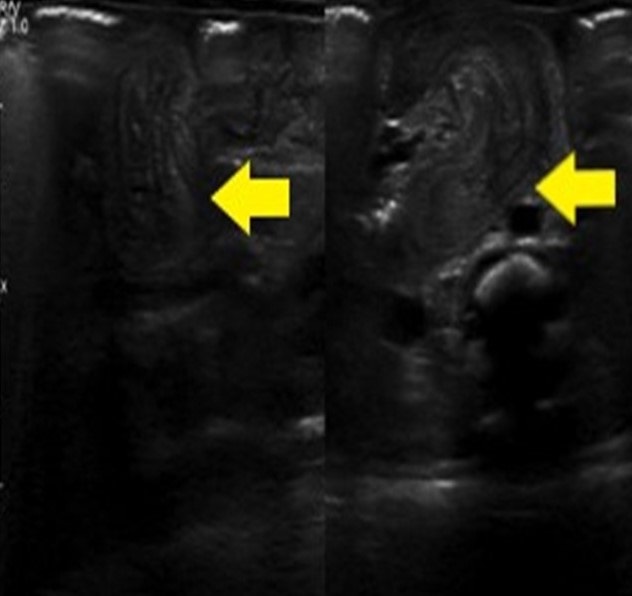

Figure 1

Abdominal Ultrasound. Transversal cut at jejunal level showing classic donut sign.

A female newborn with a birth weight of 1970 grams was delivered at 33 weeks of gestation, by cesarean section due to premature rupture of membranes. Mother had a positive history of substance abuse (opioids). The baby developed type I respiratory failure at birth and was given intratracheal phospholipids. The baby was transferred to our hospital on mechanical ventilation on day 8 of life. At presentation, the baby had a heart rate of 152/minute, a temperature of 36.9℃, blood pressure of 69/45 mm Hg, and O2 saturation of 94%. The abdomen was soft on examination, without any palpable mass, with bilious aspirates from the orogastric catheter. A plain abdominal x-ray revealed dilated bowel loops. An upper gastrointestinal (GI) series with hydro-soluble contrast was normal. Laboratory investigations showed a white blood cell (WBC) count of 18.9 x 103/L, C - reactive protein (CRP) 0.75 mg/dl, procalcitonin (PCT) 0.25 ng/dl, and a positive fecal occult blood test. After 24 hours of observation, the baby still had bilious aspirates and 2 currant-jelly stools. An abdominal ultrasound was suggestive of intussusception (Fig. 1).

Intestinal obstruction in neonates is characterized by bilious vomiting. It may be associated with failure to pass meconium, distention, and/or bloody or currant jelly bowel movements. In premature babies, it may be confused with necrotizing enterocolitis, due to delayed cardiopulmonary adaptation. Other differentials may include intestinal atresia, intestinal malrotation, band obstruction, Hirschsprung disease, etc. Ultrasound (US) is a non-invasive and easily available bedside tool to diagnose Intussusception. The classical findings of donut sign on USG, along with red currant-jelly stools and bilious aspirates, lead to the diagnosis of intussusception in our case.